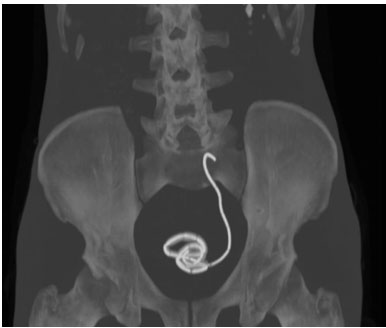

The bladder and the cecum were mobilized, the appendix was resected at the base to create a tube-like appearance, and was divided from the cecum with preservation of the mesoappendix. The appendix measured approximately 12 cm. Its distal part was anastomosed to the renal pelvis with separate stitches with 4/0 resorbable monofilament. Its proximal part was anastomosed to the bladder without creating an anti-reflux system, after placement of a transparietal mono J ureteral stent, also with separate stitches with 4/0 resorbable monofilament (Figure 1 and Figure 2).

A follow-up computed tomography urography (CTU) was performed two months after the surgery, confirming the absence of urinary fistula and the good vascularization of the appendix (Figure 3 and Figure 4).